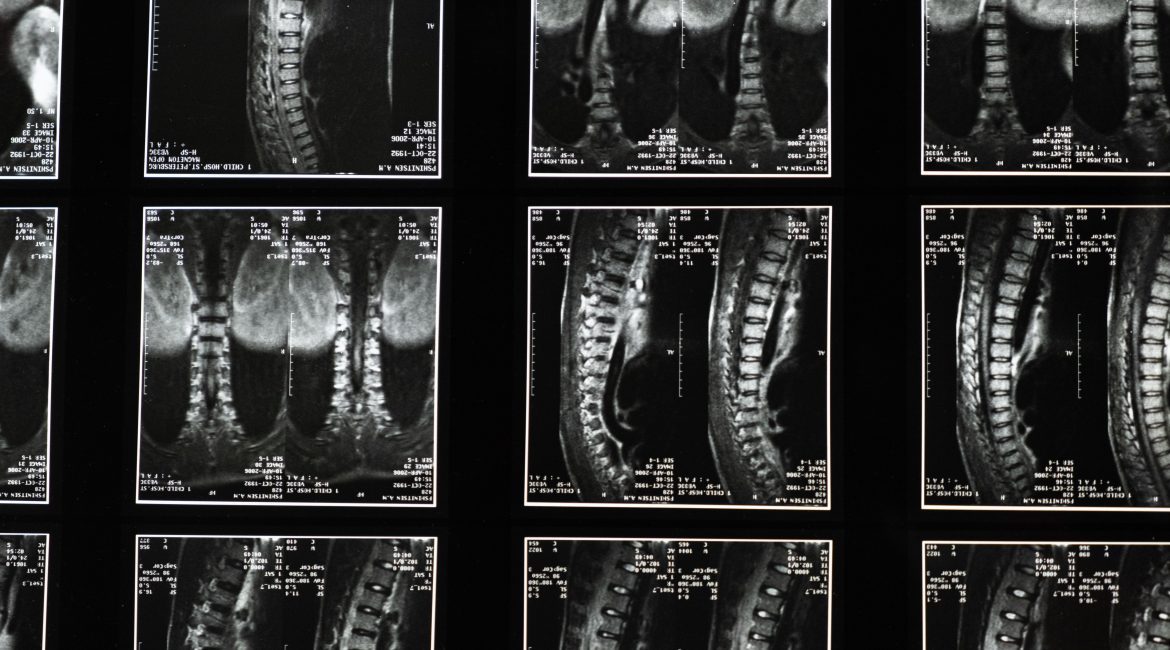

Types of Car Accident Back Injuries

If you are experiencing back pain after a car accident that continues for days, you might have a serious injury. Figuring out whether your back pain is caused by a soft tissue injury or spinal cord injury depends on symptoms. Common spinal cord injury symptoms include:

If your back pain is not caused by a spinal cord injury, see your Florida doctor. You might be suffering from a sprain, strain, or ruptured disc in your spine.